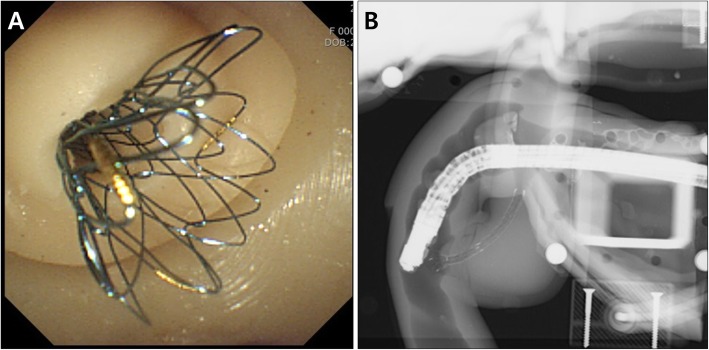

Biliary stent placement was implemented using the distal stricture and proximal dilation CBD module (Fig. 6). After the insertion of self-expandable metal stent (SEMS) (Hanarostent®, M.I.Tech, Pyeongtaek, Korea) through the stricture area, the SEMS was retrieved again, and was reinserted into the deploying catheter for repeated procedures. Plastic stent insertion and endoscopic balloon dilation were also successfully performed using the same module.

Bile duct stone extraction was also successfully implemented using the CBD dilation module. Before the procedure, we inserted a 12 mm cholesterol stone, into the module, which was obtained from a surgically resected human gallbladder. After capturing the stone by a conventional basket catheter (Flower Basket V™, Olympus Co.), the stone was pulled out from the ampulla by using a flip down technique (Fig. 7a and b). The ampullary orifice of the module was well-extended without sphincterotomy, and it was not damaged after the stone removal. Mechanical lithotripsy with a lithotripsy basket catheter (Trapezoid™ RX, Boston Scientific Co., Natick, MA.) was also successfully implemented using the distal stricture and proximal dilation CBD module (Fig. 7c).